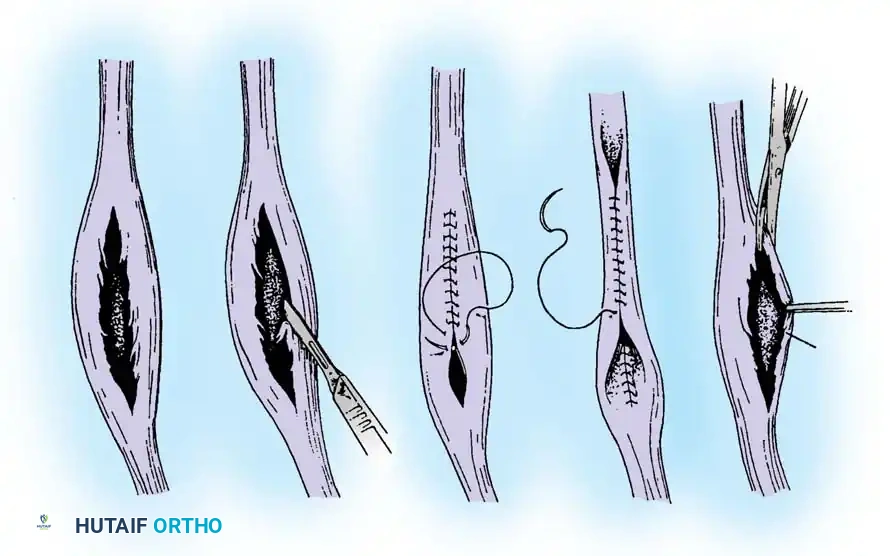

5. Tendon Repair Based on Tear Grade

For Grade I Tears (≤ 50% involvement):

If the tear involves less than 50% of the tendon's cross-sectional area, excise the smaller, degenerative section of the tendon completely. The remaining viable portion is then tubularized to restore a smooth gliding surface. This is achieved using a running 3-0 absorbable, braided suture, burying the knots to minimize friction.

For Grade II Tears (> 50% involvement):

If more than 50% of the peroneus brevis tendon is disrupted and fissured, the remaining section is generally too attenuated to be tubularized effectively. In this scenario, resect the entire diseased segment of the peroneus brevis.

Perform a side-to-side tenodesis of the proximal and distal stumps of the peroneus brevis to the intact peroneus longus tendon.

* The proximal tenodesis should be performed well above the level of the SPR, approximately 3 to 4 cm proximal to the ankle joint, generally at the musculotendinous junction of the peroneus brevis.

* Complete the repair using 2-0 nonabsorbable, braided sutures (e.g., Ethibond or FiberWire), ensuring appropriate tension is maintained to preserve eversion strength.